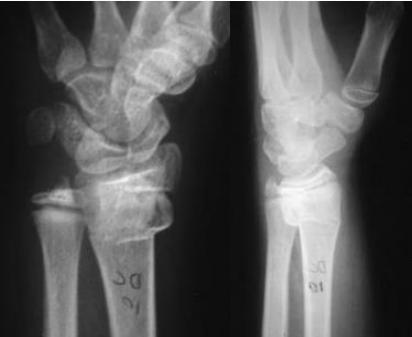

Injury films

Injured and uninjured wrists after premature physeal closure

Case Example: 12-year-old male, Salter-Harris Type II